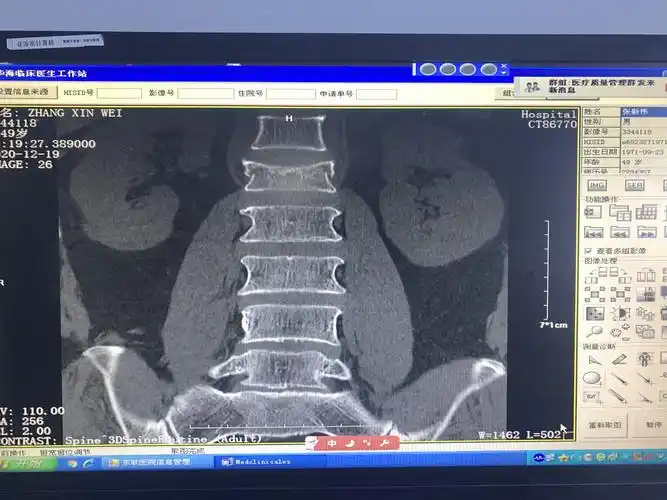

腰1椎体压缩性爆裂性骨折伴不全瘫患者手术后康复出院.

38床, 腰1椎体压缩性骨折

来我院影像检查提示:腰1椎体压缩性骨折.

术前磁共振提示,腰1椎体压缩性骨折

腰椎平片提示腰1椎体前缘压缩有二分之一,侧位片非常明显,且腰椎ct